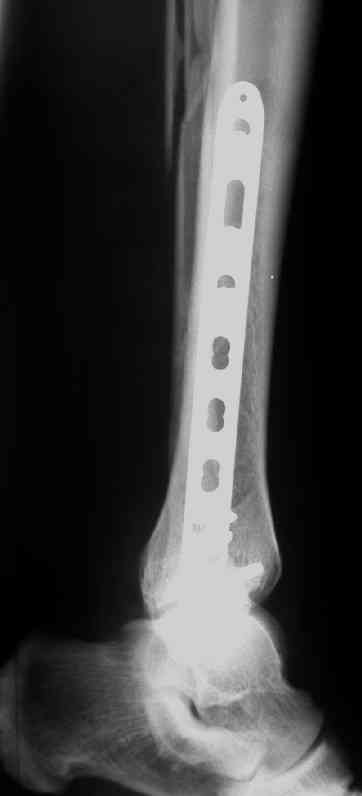

Выполнил MIPO предизогнутой метафизарной LCP

И все же немного критики:1) Вы добивались анатомичной репозиции, которая требует абсолютной стабильности, которая в свою очередь возможноа только в условиях межфрагментарной компрессии. Пластина уложена как мостовидная, не хватает стягивающнго винта. 2) есть укорочение малоберцовой кости, необхордимо восстановить ее длину! В таком виде я бы не стал разрешать раннюю нагрузку. Добавить самую малость: стягивающий винт и остеосинтез малоберцовой кости и больной может наступать сразу.

В этом случае остеосинтез выполнялся малоинвазивно и я не добивался абсолютной стабильности преднамеренно. Стабильность относительная и ст. её зависит от механических свойств импланта;возможно, нужно было взять длиннее пластину, увеличив её рабочую длину

Все справедливо для оскольчатого перелома, когда вы не добиваетесь анатомичной репозиции. При простом переломе адекватной будет анатомичная репозиция, и она у Вас получилась закрыто. Если Вы изначально предполагали относительную стабильность, то штифт позволил бы более раннюю и агрессивную реабилитацию

М\б кость укорочена, а это создает предпосылки к вторичной вальгусной деформации даже с LCP, спросите у Виталия Дрягина.